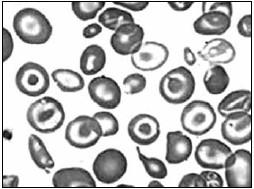

Foi solicitada uma curva de fragilidade osmótica a uma criança de 2 anos de idade, após a mãe descrever ao médico generalista a dificuldade de seu filho ter boa qualidade de vida devido às suas repetidas internações, quadros de infecções e anemia, sem sucesso após terapia com ferro. O esfregaço sanguíneo revelou poiquilocitose com presença de hemácias em alvo, hipocromia e anisocitose. Avaliando a curva de fragilidade osmótica, sugere-se um quadro de:

(Laudo e imagem cedidos pelo Laboratório de Análises Clínicas do Centro Universitário FMABC)